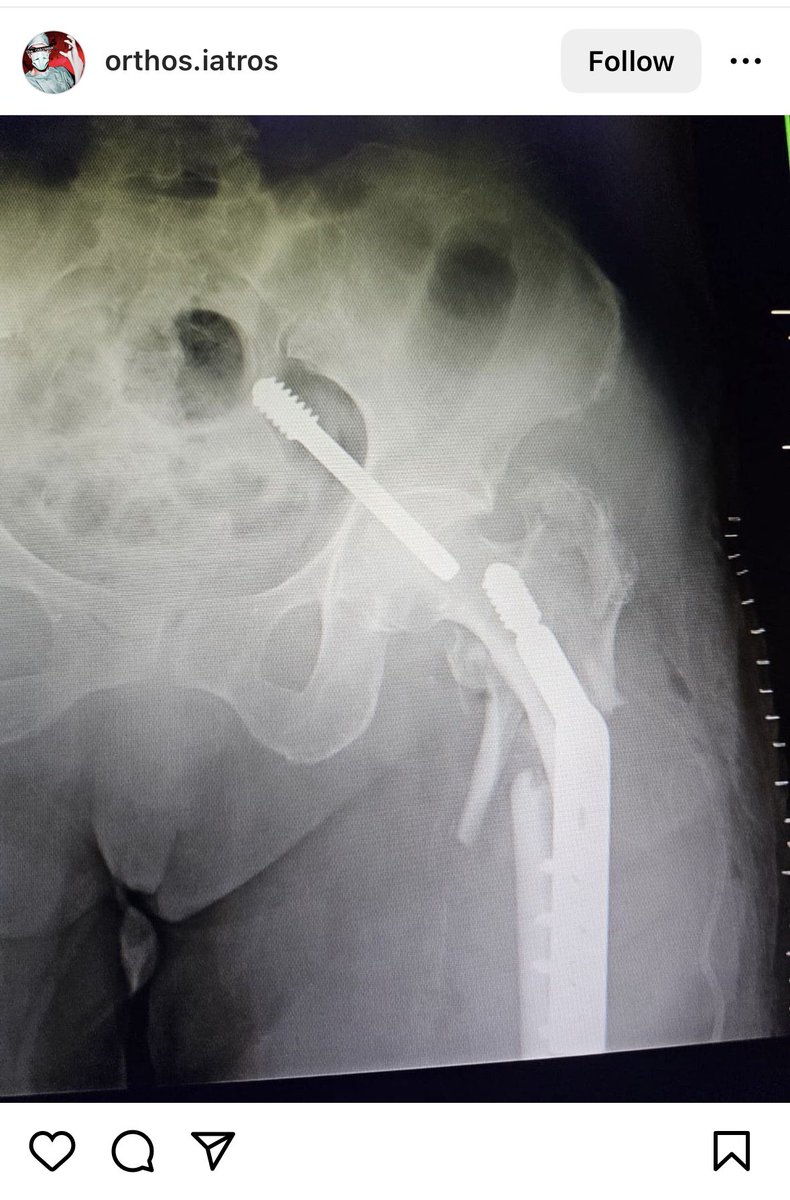

Borrowed this image from @instagram and shared on @LinkedIn Debate has ensued of whether this is real or #AI generated What says #orthotwitter

@generalorthomd @InvictaOrtho